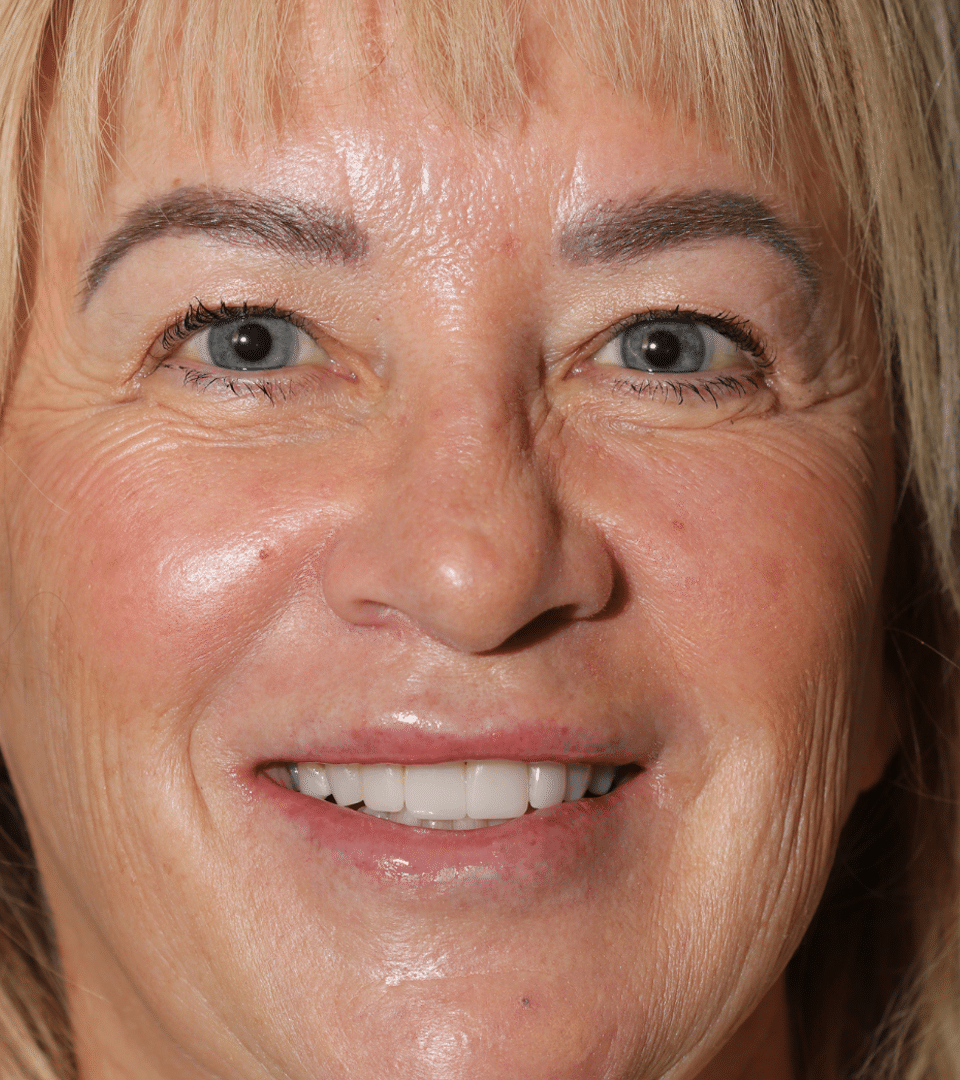

View Angle: front

Before

Before

After

After